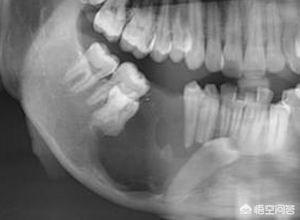

4. les lésions telles que les tumeurs kystiques des mâchoires.Lorsque des kystes, des tumeurs ou d'autres lésions dans l'os de la mâchoire qui renferme les dents altèrent considérablement la qualité de l'os de la mâchoire, les dents situées dans la zone de la lésion se déchaussent.

Options thérapeutiques : traitement chirurgical des lésions de la mâchoire, extraction des dents dans la zone focale ou chirurgie apicale.

Le déchaussement des dents peut être dû à diverses raisons, les plus importantes étant les traumatismes dentaires et la parodontite.Parmi les autres étiologies figurent les tumeurs intra-mandibulaires dans la région apicale, les maladies systémiques, les traumatismes occlusaux locaux et l'inflammation périapicale, qui nécessitent tous une attention particulière.